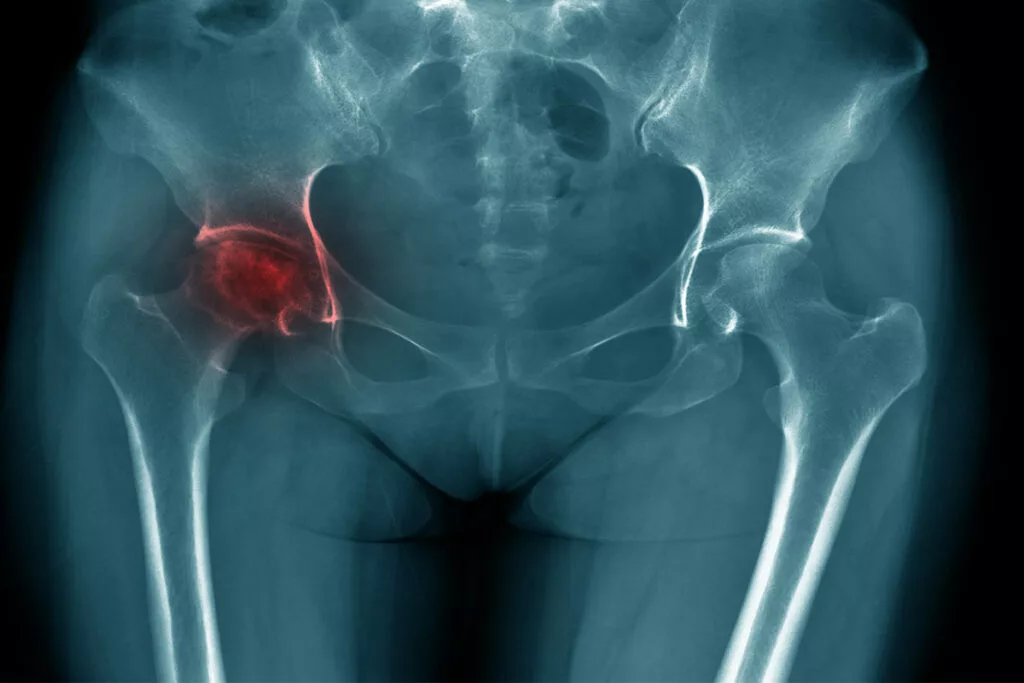

La nécrose de hanche correspond à la mort d’une partie plus ou moins volumineuse de la tête du fémur secondaire à une obstruction des vaisseaux alimentant le fémur. Elle entraîne une déformation de la tête fémorale et secondairement, une arthrose de hanche.

Un bilan radiographique standard de la hanche douloureuse permet de faire le diagnostic d’une nécrose de hanche évoluée. Dans les formes débutantes, il est nécessaire de recourir à l’IRM de hanche. Celle-ci permet également de déterminer la sévérité de la nécrose, son étendue et d’établir un bilan pronostic.